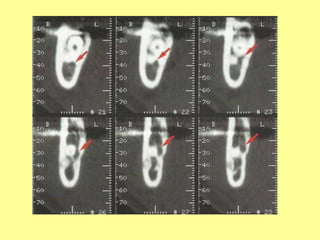

PREVENTION OF NERVE INJURIES

• Use of computed tomography to determine

the exact location of M3 and IAC (arrows).

• Multiple orientations (sagittal, axial, coronal)

give exact information to assist the clinician in

decisions regarding planning for partial or

complete M3 removal.

1)Imaging guided operativeprocedure • Use of computed tomography to determine the exact location of M3 and IAC (arrows). • Multiple orientations (sagittal, axial, coronal) give exact information to assist the clinician in decisions regarding planning for partial or complete M3 removal.